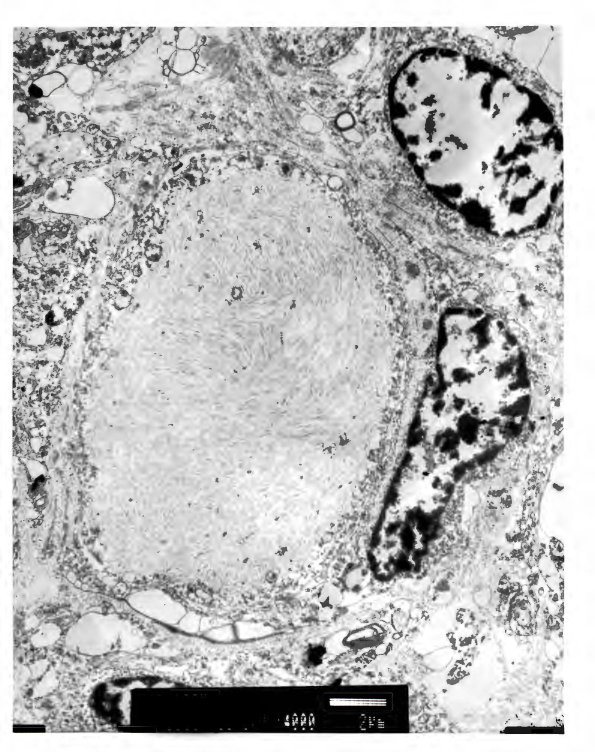

Dystrophic swellings correspond with neurofilament containing argyrophilic spheroids. (electron micrograph)